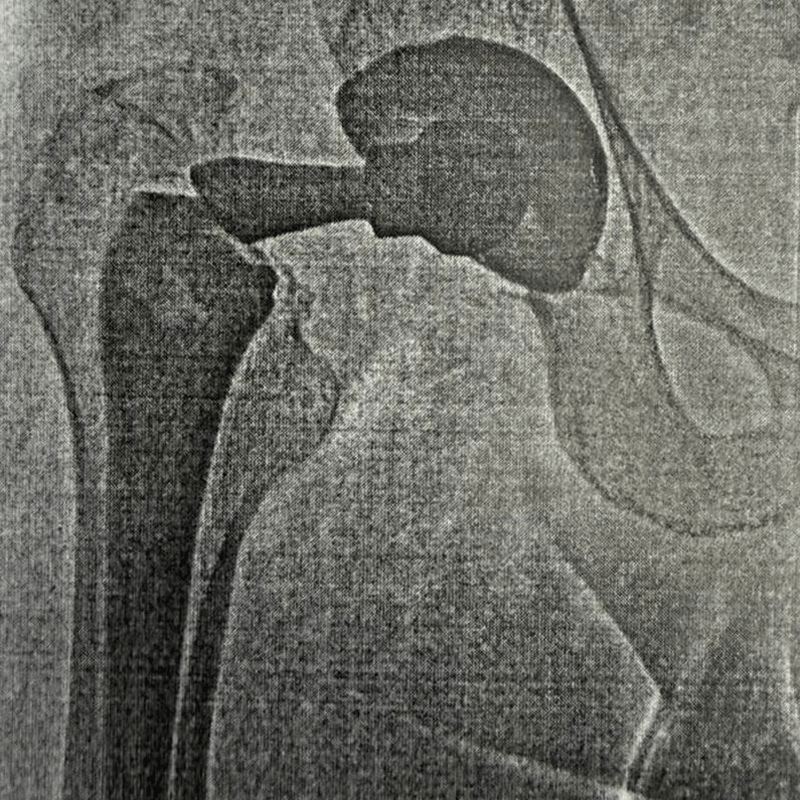

До До операции Эндопротезирование

После После замены сустава

Сложная операция. Пациент на ногах уже через 24 часа

Снова на ногах за 1 день: спасение сустава после поломки старого протеза

Тарасов Евгений Петрович

«К нам часто обращаются пациенты с осложнениями после операций в других клиниках. В этом случае счет шел на дни: сломанный старый протез разрушал кость и причинял невыносимую боль. Но современные технологии позволяют нам решать даже такие сложные задачи быстро и безопасно».

Тарасов Евгений Петрович, хирург-ортопед

• Пациент: Мужчина, 36 лет.

• Проблема: Острая боль и укорочение ноги. Диагностирован перелом старого протеза (установленного 16 лет назад в другой клинике). Детали мигрировали и разрушали сустав.

• Наше решение: Экстренное удаление сломанных элементов и установка современной ревизионной системы.

• Результат: Боль ушла сразу после операции. В первые сутки пациент встал на ноги и начал ходить с опорой на костыли.